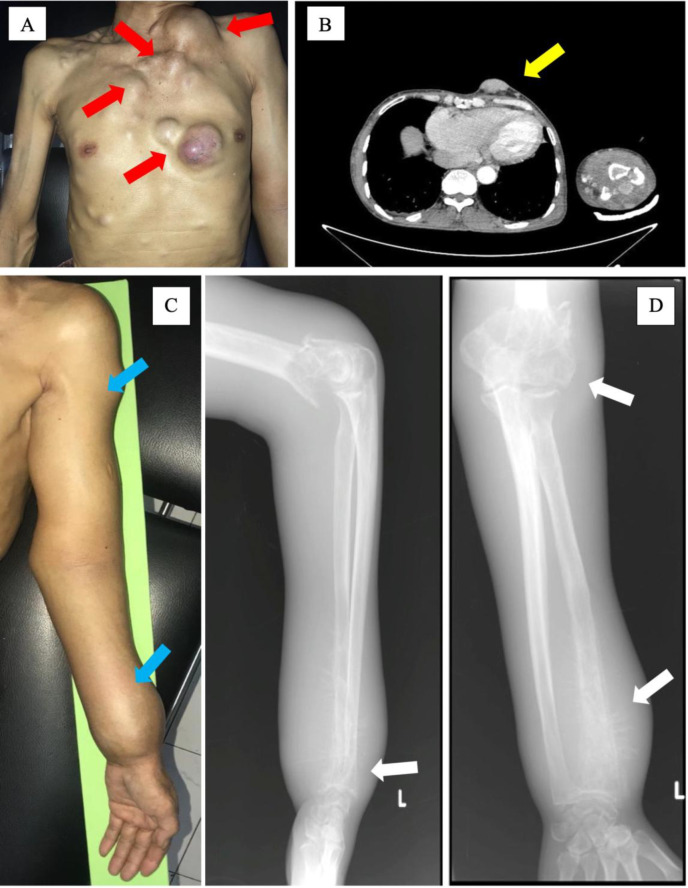

Case presentation: A 49-year-old man presented with multiple subcutaneous soft tissue nodules in the thoracic area and multiple pathological fractures in the left distal humerus and distal ulna. Clinical and radiological findings were suggestive of metastatic bone disease with differential diagnosis of multiple myeloma. Fine needle aspiration biopsy and histopathological findings were suggestive of multiple myeloma with differential diagnoses of metastatic carcinoma, rhabdomyosarcoma, and amelanotic melanoma. Thus, immunostaining for CD138, CK, desmin, vimentin, S-100, and HMB45 were requested and the results were compatible with the final diagnosis of amelanotic plasma melanoma.